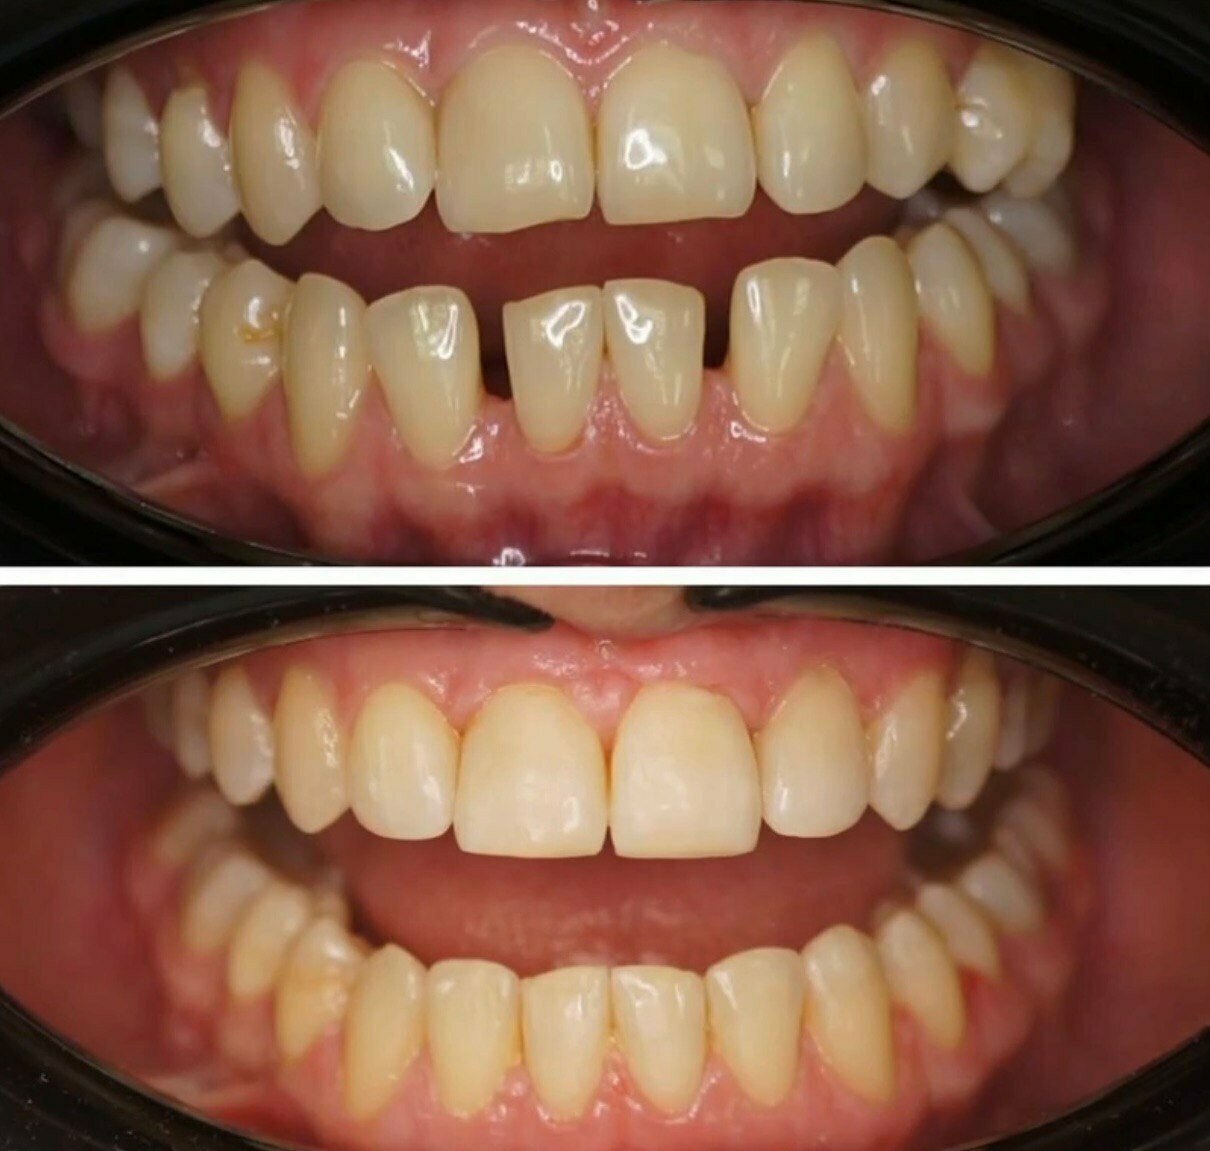

Gold Dent специализируется на различных направлениях стоматологии: общей терапии, хирургии, ортодонтии, эстетической и детской стоматологии, имплантологии, протезировании и эндодонтии. В клинике применяются передовые технологии, такие как цифровая стоматология CAD/CAM, лечение под микроскопом, компьютерная томография и костная пластика.

Клиника соответствует требованиям Росздравнадзора и обеспечивает пациентам не только здоровую, но и красивую улыбку.

- Долговечные и эстетичные результаты (импланты, протезы).

Приходила на очередной осмотр, прошло уже больше 5 лет как Гилязов Булат Ильгизович установил мне мои зубы. К зубам быстро привыкла, своих зубов оставалось очень мало, наверное, 5 зубов всего, думала, что и их придется удалить, были некрасивые, разрушенные. Булат Ильгизович сказал, что в моем случае надо сохранить все зубы, которые хотябы еще могут прослужить больше 5 лет, так как у меня очень маленькие кости и возможности установить импланты нет. Наращивать кость в моем случае тоже было нежелательно. Несмотря на такую ситуацию зубы получились очень даже хорошими, по цвету натурально белоснежные, ровненькие, постоянно спрашивают кто мне сделал такие красивые зубы. Я очень благодарна за такую безупречную работу, потому что много у кого вставные зубы выглядят как не живые, большие. Желаю процветания клиники, врачам, каждый год прихожу на осмотр, делаем чистки, бережем, что осталось.